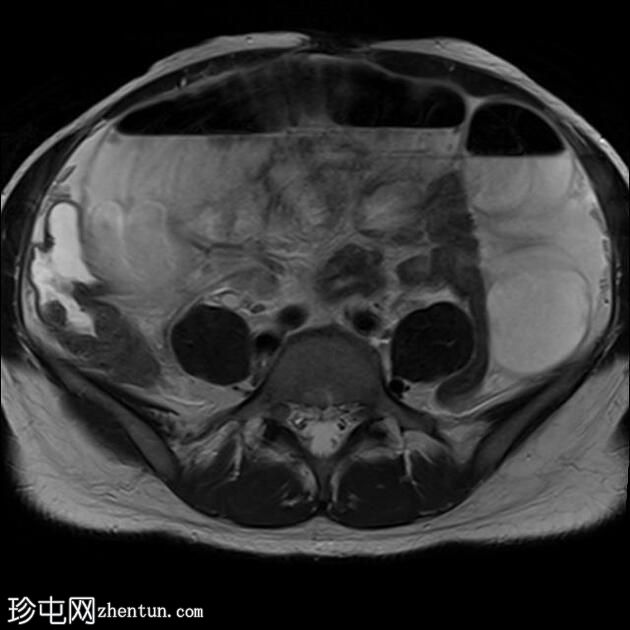

轴位

T2加权像

T2加权像显示复杂囊性肿块,内含出血性物质,右侧卵巢未显影。注意卵巢蒂扭转。

盆腔内可见分层血液成分。